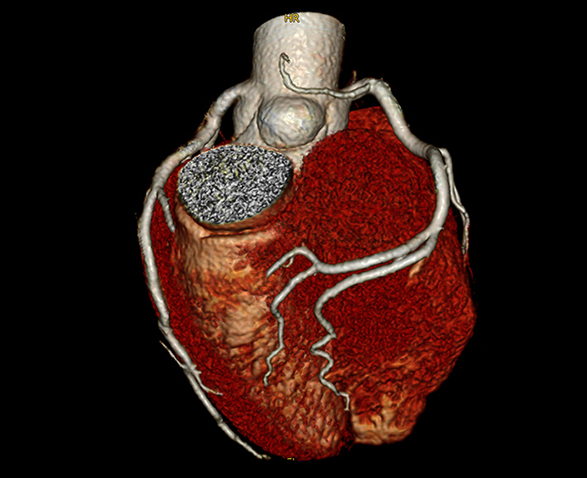

- Dėl itin greito 0,259 s sukimosi greičio „NeuViz Prime“ galima gauti tikslesnius vaizdus kraujotakos sistemoje.

EKG dozės moduliacija – šis rinkoje pirmaujantis iteracinis rekonstrukcijos sprendimas užtikrina maksimalų dozės sumažinimą nepabloginant vaizdo kokybės ar atkūrimo greičio.